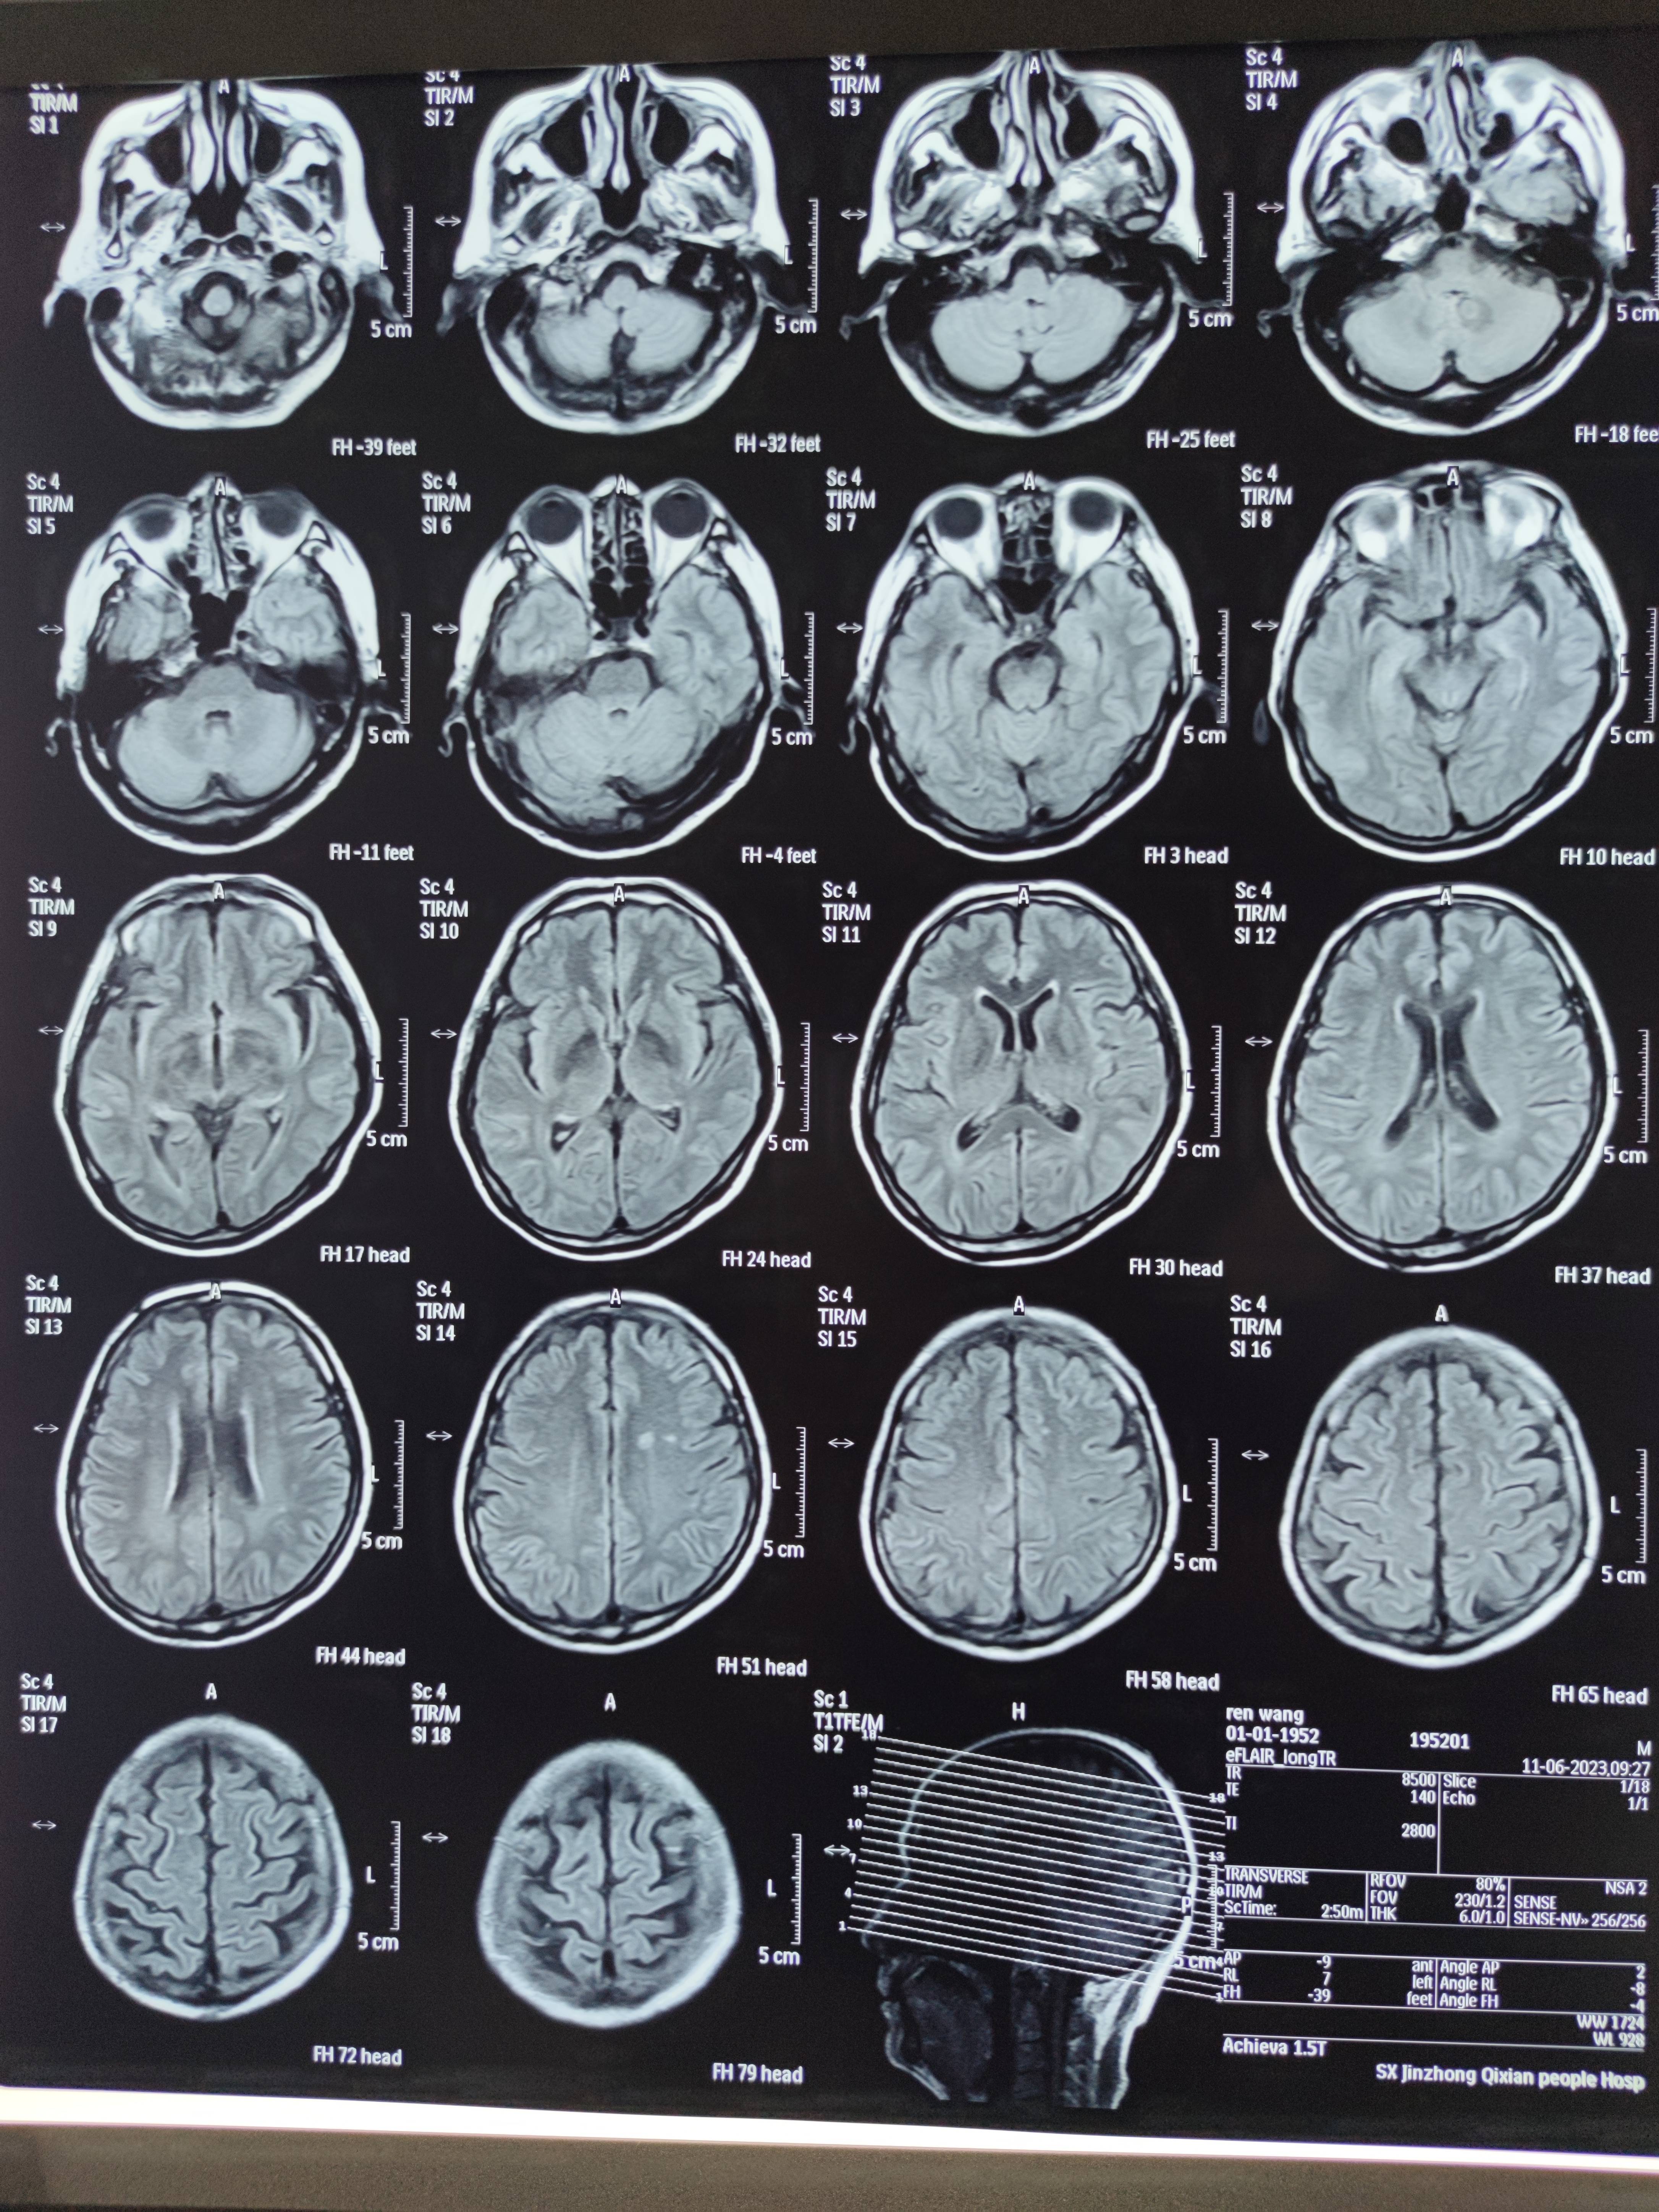

四月份癌胚抗原还是5.6,这个月到8了,持续升高。做了核磁增强,左侧桥小脑角哪有个地方不确定。肝脏核磁平扫弥散有两个点状高信号,转移也排不了,胃肠镜正常,左颈部有个变圆的淋巴结,保险点是不该加个化疗药了?咨询了陈波主任,等结果的吧!图片